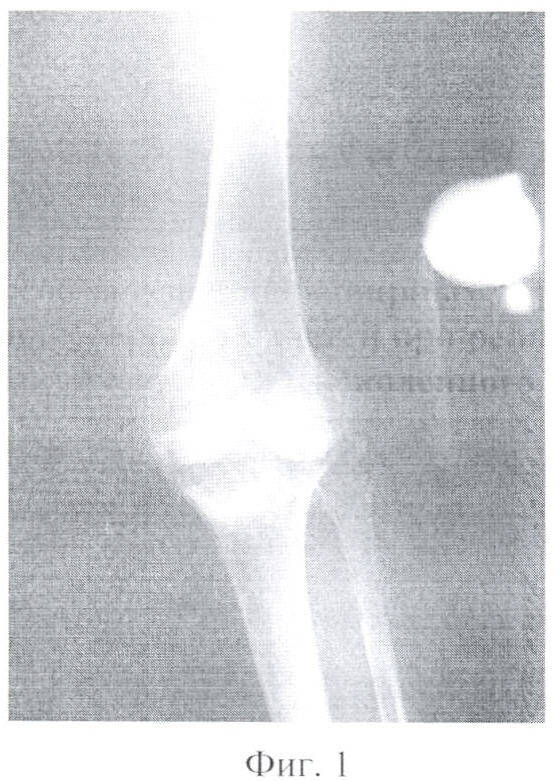

Фигура 1 – рентгенограмма левого коленного сустава в прямой проекции пациентки, страдающей ревматоидным артритом.

Фигура 2 – рентгенограмма левого коленного сустава в боковой проекции пациентки, страдающей ревматоидным артритом.

По поводу ревматоидного поражения левого коленного сустава в 2003 году выполнено тотальное эндопротезирование левого коленного сустава эндопротезом «Феникс» (фиг.1, 2, 3).